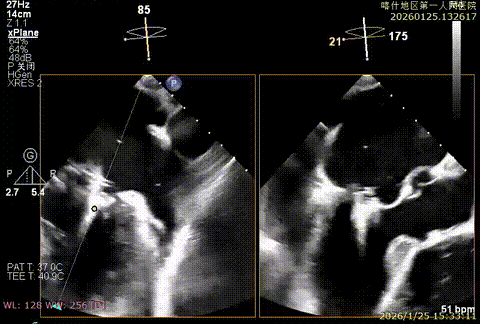

该例患者为VFMR,术前制定手术策略:患者二尖瓣重度反流,后叶严重栓系,心房心室扩大。患者瓣口面积4.5cm2,预计使用两枚XTR解决患者瓣叶脱垂和反流。考虑到先于2区进行钳夹,应该能获得足够的房间隔穿刺高度。术中经不断调整穿刺位点,最终穿刺高度4.4cm。成功穿刺后将第一枚XTR送入二尖瓣正上方,进行弹道测试Orientation调整后,最终定位于2区正上方下左心室。第一枚夹子在左室成功捕捞和钳夹瓣叶后,瓣叶反流程度显著降低,夹子外侧仍见部分反流,随后在第一枚夹子外侧再次放置一枚XTR,瓣叶反流程度进一步降低至微量。通过TEE观察,二尖瓣双孔组织桥稳定,跨瓣压差3mmHg,肺静脉逆流改善明显,手术安全结束。

X-plan重度反流

3D enface后叶栓系

3D enface观察反流